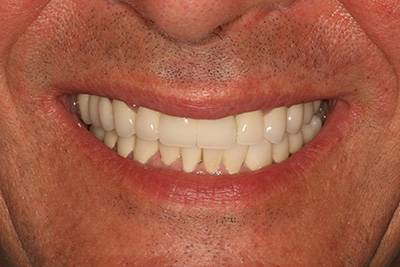

1. eset

A páciens fogágybetegség miatt érkezett hozzánk. A felső fogak menthetetlen állapotban voltak. All on 6 megoldásként a felső fogak eltávolításakor 6 implantátum került beültetésre és a páciens azonnal egy fix ideiglenes hidat kapott. 4 hónapos gyógyulási idő után készült el a felső fémkerámia leplezésű körhíd.